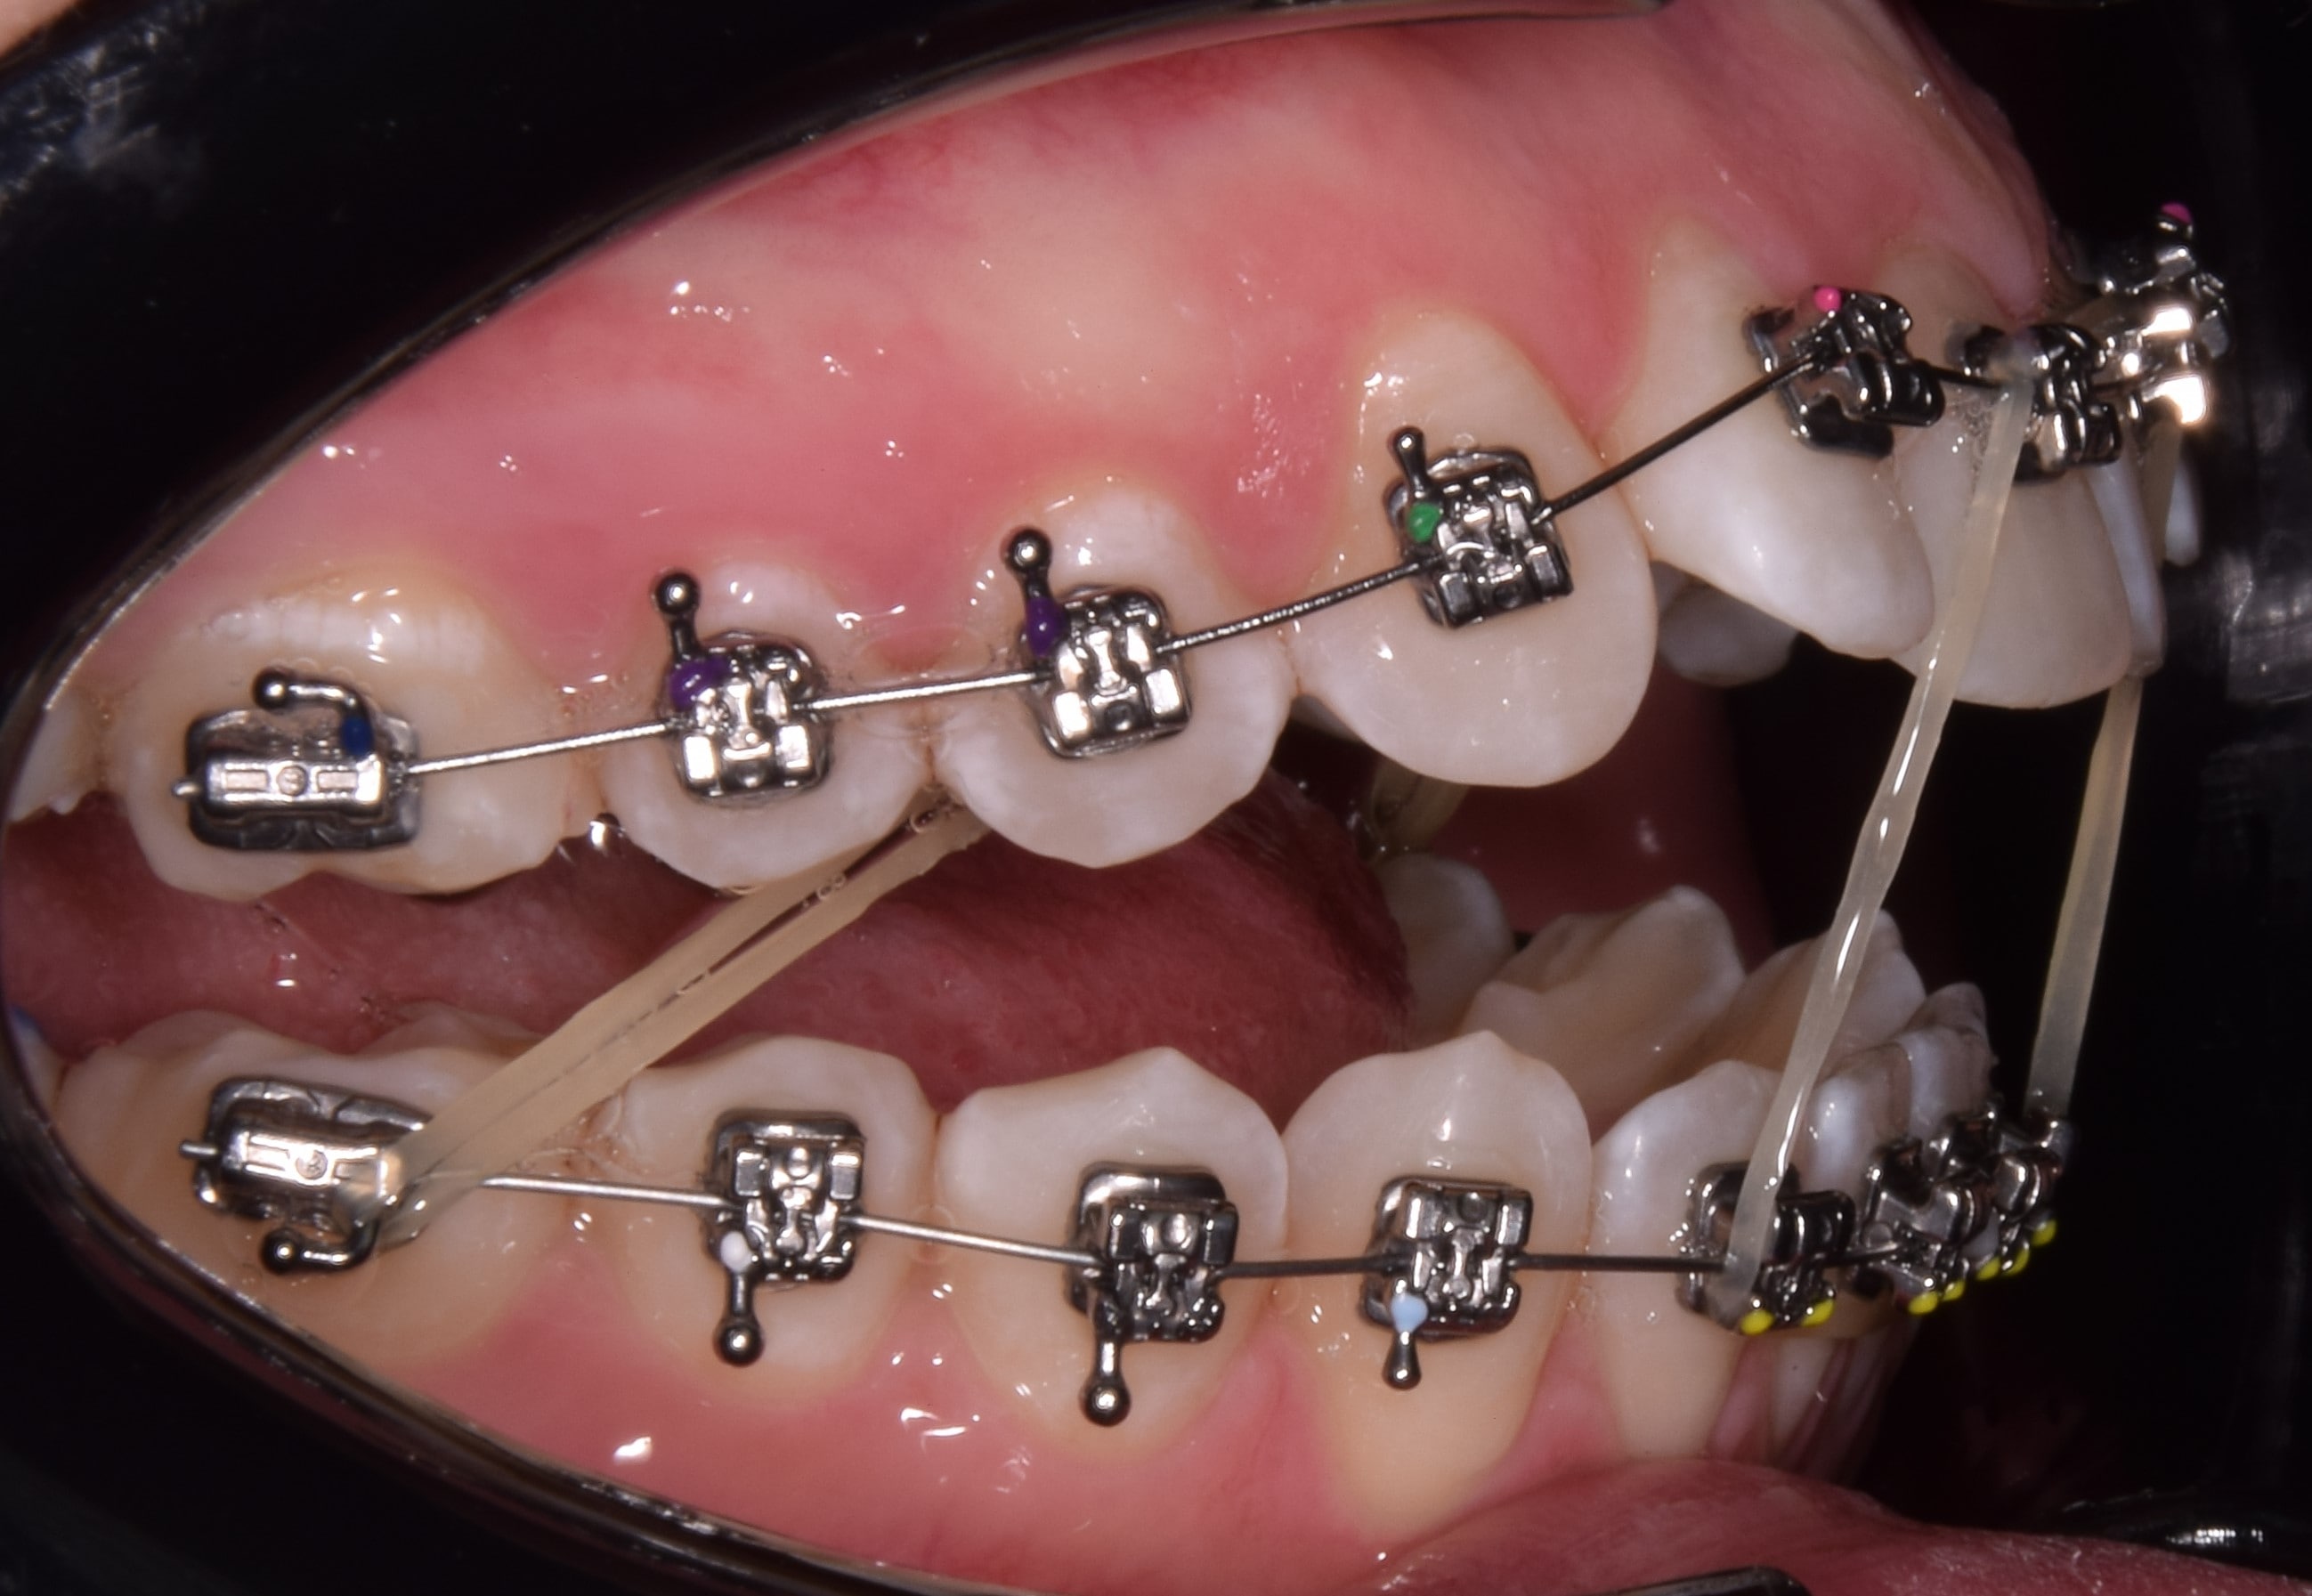

Bracket

Bracketnek nevezzük a rögzített fogszabályzó készülék fogakra ragasztott alkotóelemét, melyekbe a fogszabályzó ívet valamilyen módszerrel rögzítjük. Kisőrlőtől-kisőrlőig dolgozunk bracketekkel, a nagyőrlőkön már tubusok vannak. A bracketek (tappancsok) fogakkal érintkező talpa érdes, hálós szerkezetű, mely jobb rögzülést biztosít. Elsősorban az oldalsó bracketeken (nagyőrlők, kisőrlők, szemfogak), található speciális kampó is. Erre különböző kiegészítő eszközöket akaszthatunk (intermaxilláris gumihúzás, füzérgumi, húzórugó stb.). Anyaga szerint beszélhetünk fém, kerámia, műanyag és arany bracketekről. Az ív rögzítésének típusa szerint megkülönböztetünk hagyományos (az ívet gumival rögzítjük a bracketbe), illetve önligírozó bracketeket (nyitó-záró szerkezettel rögzítjük az ívet).

Intermaxilláris gumihúzás

A kezelések során végig elasztikus gumihúzást használunk. Ezek egyszerű, Ön által a bracketekre felhelyezhető gumikarikák, melyeket a nap 24 órájában (!!) hordani kell az általam előírt módon. A gumikat csak fogmosáskor és étkezéskor lehet eltávolítani. Érdemes lefekvés előtt új gumikarikát felhelyezni, hiszen a nap folyamán fáradás figyelhető meg az anyagban. FIGYELEM! A gumihúzás a kezelés sikerességének alappillére. A gumihúzások nem előírás szerinti használata a kezelési idő meghosszabbodásához vezet, valamint sokszor lehetetlenné teszi a tökéletes végeredmény kialakítását. Hordásuk a megszokási időszakban picit macerás, de alapfeltétele a gyors, tökéletes végeredmény elérésének.